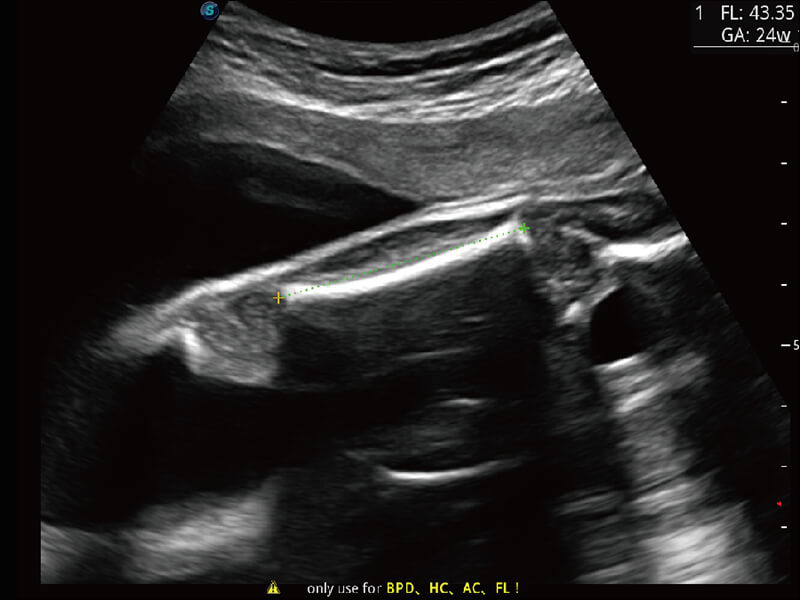

性能优异的硬件架构,极大提升超声系统的运行效率和数据处理能力。相比以往超声成像系统,Wis+平台为您带来极快的响应速度和成像帧频,提升检查流畅度。

S60探头工艺,从前端信号处理每一个环节采集无损声学数据,真实还原组织原貌,再现解剖细节。